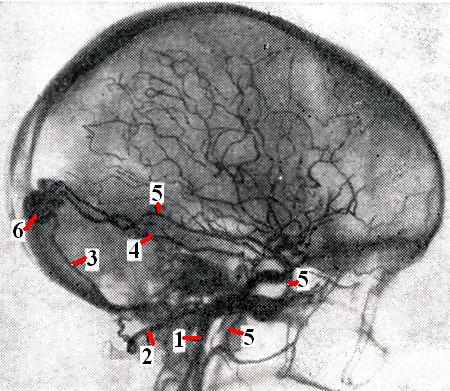

Рис. 3.

Артерио-синусное соустье (6) в области слияния синусов: 1 — внутренняя сонная артерия; 2 — расширенная затылочная артерия; 3 — ветвь затылочной артерии; 4 — передняя менингеальная артерия; 5 — расширенная средняя менингеальная артерия.